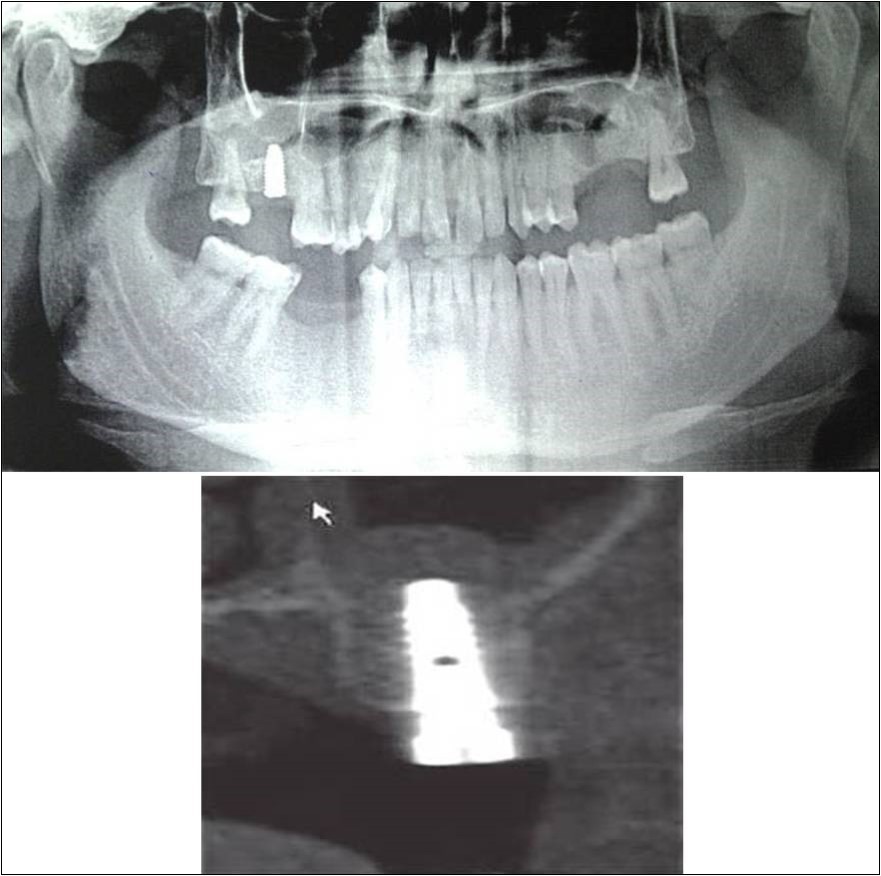

Case Report 4:

A 19 years old young female patient reported to the Department of Oral and Maxillofacial Surgery, D.A.P.M.R.V Dental College and Hospital seeking options for replacement of her missing right and left upper first molars with a fixed prosthesis as she was uncomfortable with the removable partial denture i.r.t 16 and 26. The teeth were extracted 6 months ago because of gross loss of crown structure and poor prognosis for root canal treatment. Patient was also undergoing fixed orthodontic treatment for proclined upper anteriors. Patient did not give history of any existing sinus pathologies. All possible rehabilitative options were explained to the patient and a treatment plan of replacement of missing teeth with implant supported prosthesis using two dental implants was finalized.

Clinical and Radiological Assessment:

1.Partially edentulous maxillary arch with missing 16 and 26;

2.Increased pneumatisation of right and left maxillary sinus;

3.Height of available bone-

16 region: 6.5mm;

26 region: 6.2mm;

4.Transverse thickness of available bone (CBCT evaluation)-

16 region: 8.3mm;

26 region: 10.5mm;

5.Fixed orthodontic appliance;

6.Inter-ridge space adequate to place implant (11mm).

Treatment:

Patient underwent the procedure of indirect sinus elevation using sinus osteotomes in relation to 26 region. Calcium phosphosilicate putty was dispensed as the graft material through the crestal osteotomy site to maintain the elevated sinus membrane followed by placement of 5 x 10mm dental implant under local anaesthesia and strict aseptic protocols. The implant was allowed to osseo-integrate for a period of six months during which the patient was followed-up periodically and was assessed for peri-implantitis, crestal bone loss and mobility. Patient was taken-up for direct sinus elevation via lateral window approach for sinus augmentation i.r.t 16 region. Under aseptic conditions and local anaesthesia, lateral wall of maxilla was exposed after muco-periosteal flap elevation. A window was created of 1cm diameter corresponding to apical aspect of 16. Sinus membrane was identified and elevated using sinus elevators and reamers without perforating the lining. Once the sinus membrane was elevated, phosphosilicate putty was dispensed through the lateral osteotomy site as the graft material to achieve an augmentation of 1cm assessed clinically and confirmed using post-operative OPG. At the end of 6 months, a repeat CBCT scan was advised to evaluate the increase in bone height. (Figure 13a,b, pre-treatment; Figure 14a,b, post-treatment)

Figure 13.(a,b) Pre-treatment OPG and cross section of CBCT showing residual alveolar bone height for Case No.4;

Figure 14.(a,b) Post-treatment OPG and cross section of CBCT showing residual alveolar bone height for Case No.4;

Case Report 5:

A 63 years old male patient reported to the Department of Oral and Maxillofacial Surgery, D.A.P.M.R.V Dental College and Hospital seeking options for implant prosthesis for replacement of missing teeth in upper left back tooth region. The teeth were extracted two years ago because of extensive caries and failure of root canal treated 26, 27. No prosthetic rehabilitation was carried-out in the past. Patient was a known case of diabetes mellitus since 20 years which was under control and was on medication for the same. His general health was satisfactory with no other co-morbidities. Patient did not give history of any existing sinus pathologies.

Clinical and Radiological Assessment:

1.Partially edentulous maxillary arch with missing 24, 25, 26, 27, 28;

2.Increased pneumatisation of left maxillary sinus;

3.Height of available bone- 2.5mm;

4.Transverse thickness of available bone (CBCT evaluation)- 10.9mm;

5.Inter-ridge space adequate to place implant (12mm).

Treatment:

Patient underwent the procedure of direct sinus elevation using sinus lateral approach kit. After crestal and vertical release incisions, muco-periosteal flap was raised to expose the buttress region. A bony window of 1cm diameter was created; sinus lining identified and elevated up to receive calcium phosphosilicate as graft material and closure was achieved under local anaesthesia and strict aseptic protocols. Implant placement was planned to be carried-out after a period of 6 months to allow for the consolidation for graft and naive bone formation. At the end of 6 months, a repeat CBCT scan was advised to evaluate the increase in bone height. (Figure 15a,b, pre-treatment; Figure 16a,b, post-treatment)

Figure 15.a,b. Pre-treatment OPG and cross section of CBCT showing residual alveolar bone height for Case No.5;

Figure 16.a,b. Post-treatment OPG and cross section of CBCT showing residual alveolar bone height for Case No.5;